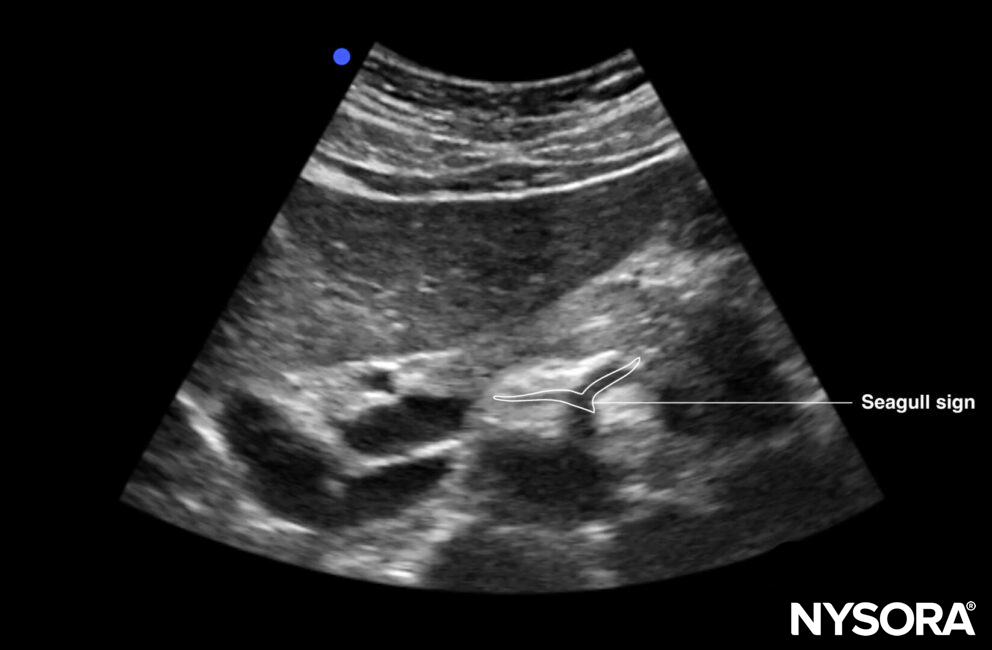

- The seagull sign refers to the celiac trunk and its division into the hepatic and splenic arteries, which appear like the wings of a seagull.

The seagull sign: the celiac trunk and its division into the hepatic and splenic arteries, which appear like the wings of a seagull.